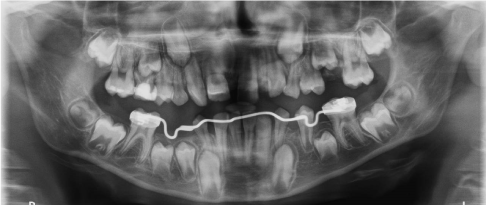

Case 1. A 10 years old male patient presented with a 1 month history of mandibular swelling on the right, asymptomatic. Performed Ortopanthomography and mandibular TCCB an osteolytic lesion is observed that extends from 8.5 to 8.2 with dislocation and retention of 43, 44 and 45 (Figure 1).

Figure 1 Case 1. Initial Ortopantomography